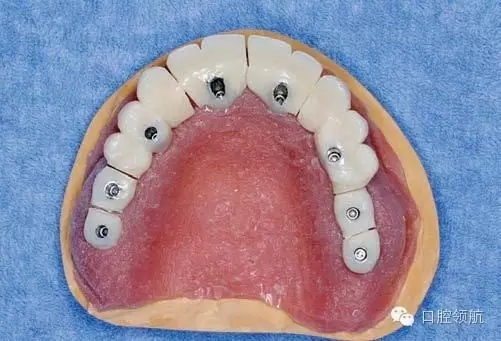

醫(yī)生在制作即刻負(fù)重的上部結(jié)構(gòu)時,應(yīng)把事先做好的臨時上部結(jié)構(gòu)(圖3)先分割開(圖4),再在口腔內(nèi)分幾次用快速聚合樹脂連接(圖5)。

圖5 在口腔內(nèi)分幾次用快速聚合樹脂連接。

各個連接部位,首先在牙頸部連接固定,充分硬化后再向牙冠方擴大固定范圍,如此逐漸連接固定,切勿一次連接,要逐漸補償聚合的收縮而操作,因為最終合計的硬化收縮量相當(dāng)大。